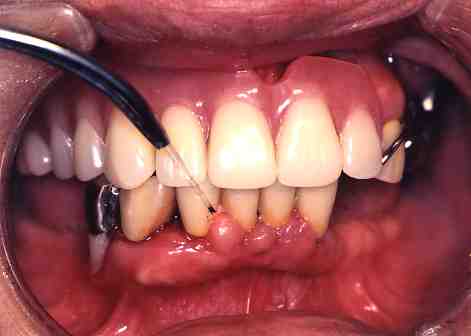

3.一週間後

歯の周りの歯ぐきの腫れも

かなりおさまりました。